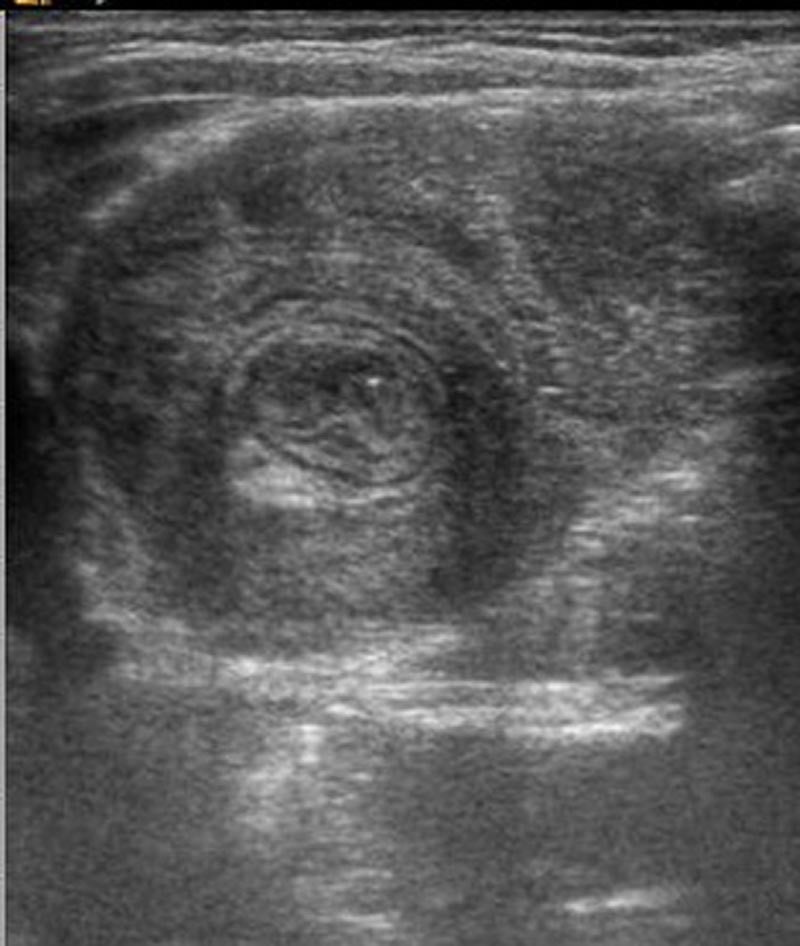

10-month-old male infant presents to the ED by EMS with vomiting and altered mental status (AMS). Infant arrives to the ED awake but poorly interactive. Ultimately, the infant will be diagnosed with intussusception and hypovolemic shock based on the history, physical exam and ultrasound findings. Learners are expected to establish a differential diagnosis of AMS appropriate for an infant, demonstrate appropriate resuscitative interventions, and use appropriate imaging and labs to help identify the cause of AMS.